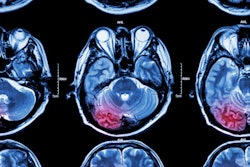

ICAS is caused by the build-up of plaque in the arteries due to atherosclerosis and is a major cause of ischemic stroke with a risk of recurrence. Endovascular revascularization therapy (stenting) has been hypothesized as a treatment, yet previous trials have shown little benefit of the procedure over medical therapy, the authors noted.

The study included 150 participants (mean age, 61 years old, 45 women) with transient ischemic attack or ischemic stroke attributed to severe ICAS who were randomized into stenting (n = 74) and medical therapy (n = 76) groups. The primary end point was a composite of transient ischemic stroke, ischemic stroke, intracranial hemorrhage, and death within 30 days or any ischemic stroke from 30 days to one year.

According to the results, stenting did not result in a reduction in ischemic stroke cumulative incidence compared with medical therapy with antiplatelet drugs at one year (stenting versus medical therapy: 12 of 74 [16%] vs. 18 of 76 [24%], p = 0.26). Stenting also did not reduce the cumulative incidence of ischemic stroke compared with medical therapy over a 10-year follow-up period, the researchers reported.